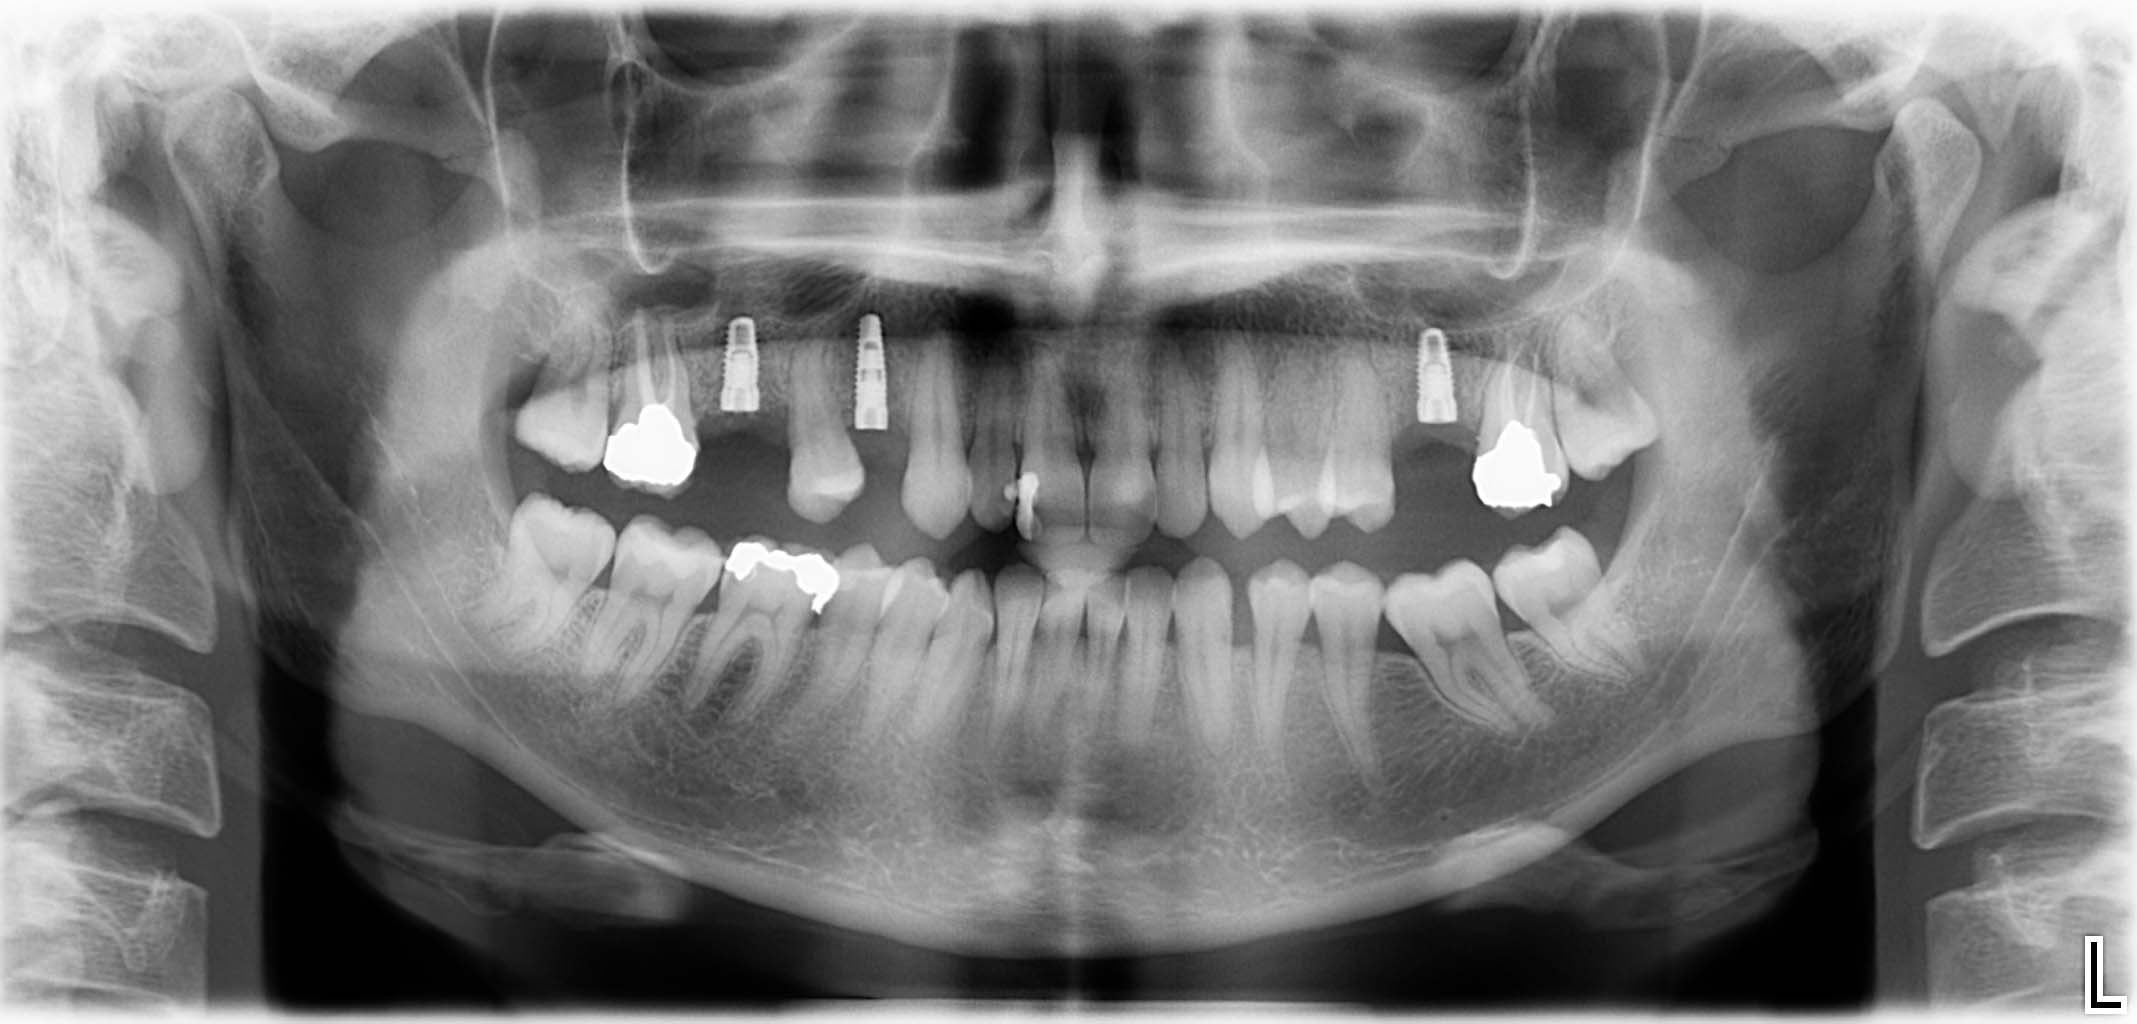

Ausgangssituation: Zahn 36 mit apikaler Beherdung, nicht erhaltungswürdig

Erfolgreich implantierte Patientenfälle (klinische Fotos)